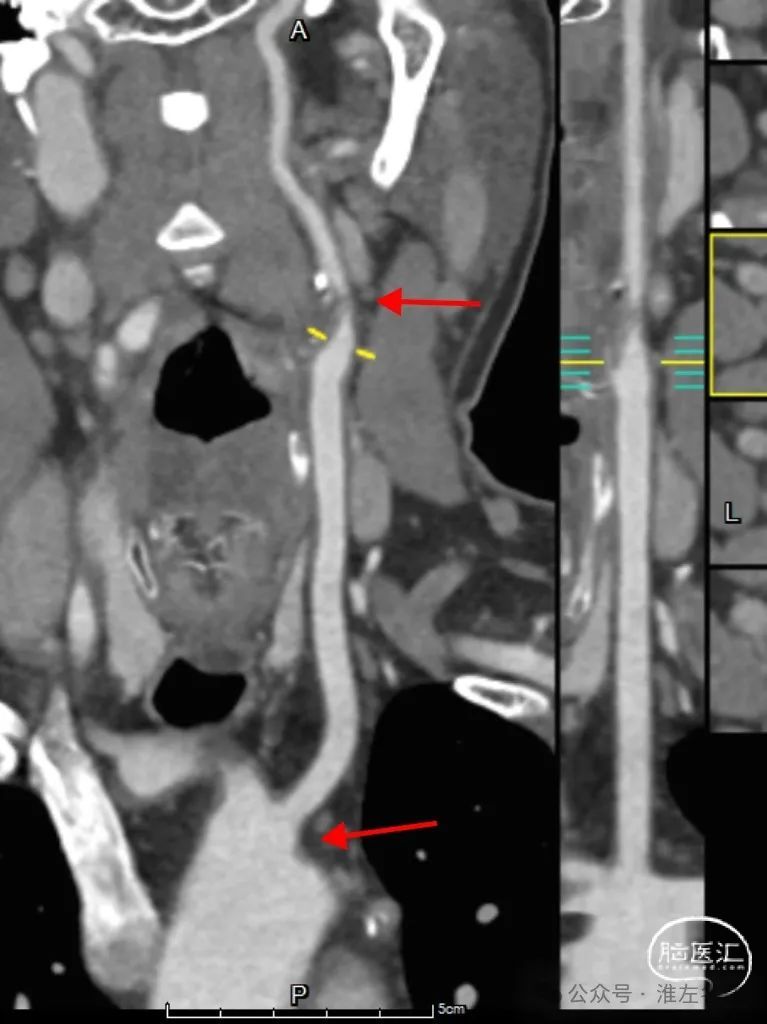

CTA:左ICA起始部重度狭窄,左CCA与无名动脉短共干,左CCA起始段走行明显向左,与主动脉弓呈显著锐角。

5F长椎管(125cm)+6F长鞘(90cm Cook)同轴,椎管头端旋调抵进共干开口,常规泥鳅导丝超选进入左CCA远端,因其近段与弓成角迂曲明显,导丝支撑不足,椎管尝试推进入左CCA失败。

更换125cm 5F预塑型西蒙管,在左锁骨下成形后,成功超选到左CCA。

西蒙管于左CCA造影,用硬泥鳅导丝超选入枕动脉,并西蒙管前推上高到枕动脉,加强上支撑,后长鞘顺利过弓,抵达左CCA远端。

建立治疗通路后,保护伞下(NAV6 4-7mm)行左侧ICA起始部狭窄支架植入(wallstent 9*40mm)。